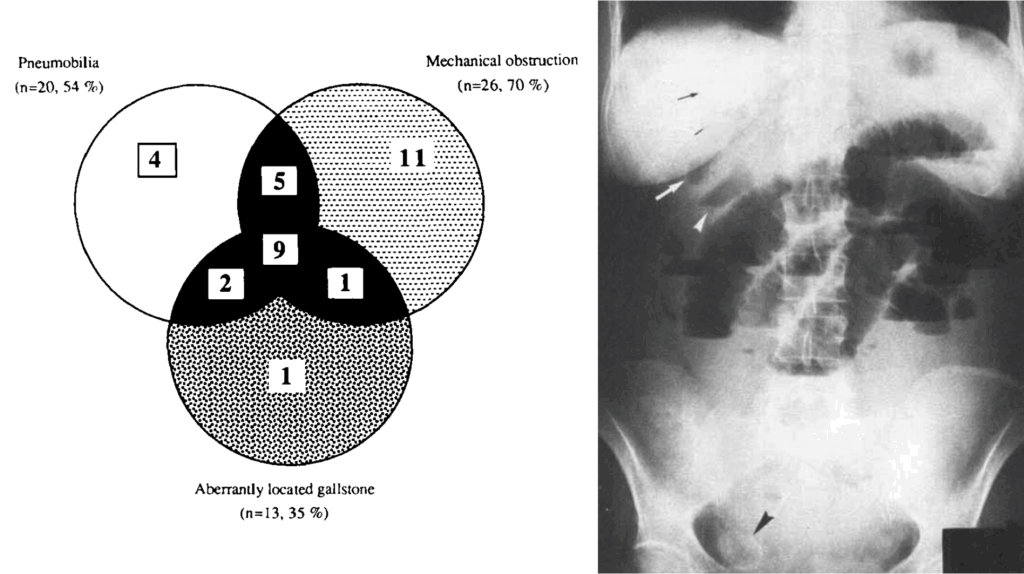

1990 – Clavien et al recorded thirty-seven patients (33 women and four men, median age 78 years) who were operated on for gallstone ileus

Right: pneumobilia (black arrows), mechanical ileus, and an aberrantly located gallstone (black arrowhead). Clavien 1990